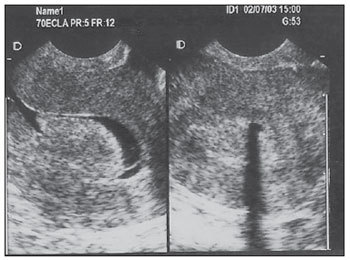

• Avaliar USG-TV (pós menopausa)

• >4-5mm sem TH

• >8mm com TH